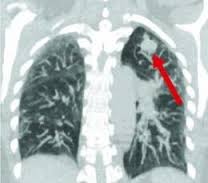

Обязательно назначают доктора рентгенографию, которая позволяет визуализировать новообразование и определить его тип. Для того чтобы обнаружить очаги развития болезни, имеющие небольшой размер, применяют компьютерный томограф. С помощью данного прибора можно также понять, распространилось ли новообразование на другие органы, а также лимфоузлы.